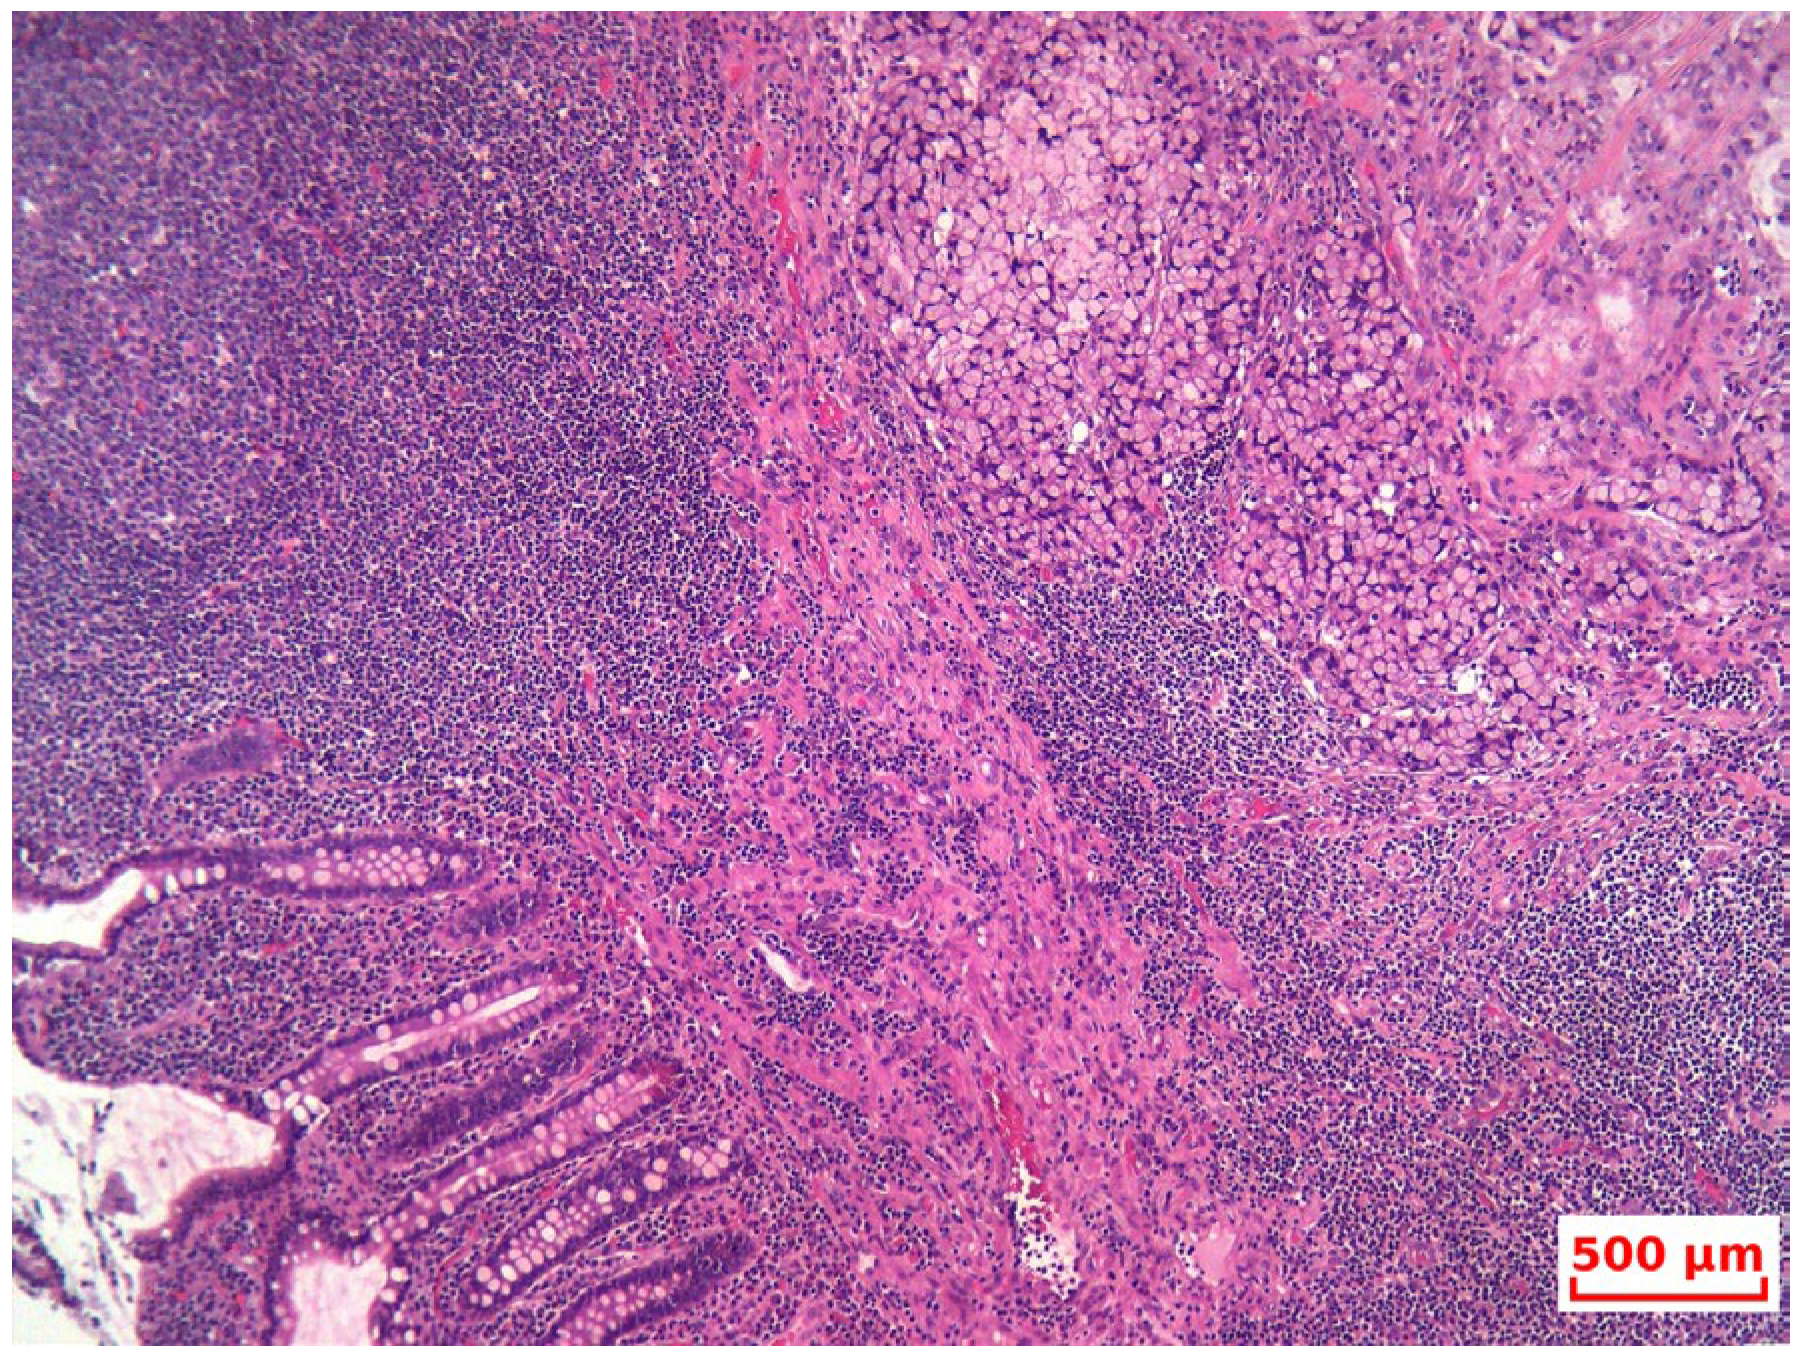

- The diagnosis of GCA was confirmed based on its characteristic histopathological features, and the non-endocrine component was verified through immunohistochemistry (IHC), although this may erroneously lead pathologists toward a NET diagnosis. Therefore, subspecialty pathology review of appendiceal neoplasms at referral centers is warranted, as emphasized by Jedrkiewicz [25].

- Diagnostic pitfalls: Goblet cell adenocarcinoma (GCA) often presents with overlapping histological features of both adenocarcinoma and neuroendocrine tumors, which can lead to misclassification as typical carcinoid or mixed adenoneuroendocrinecarcinoma (MANEC). The diagnosis requires awareness of the dual phenotype, with both glandular (mucin-secreting) and neuroendocrine features, best demonstrated by morphology and immunohistochemistry (e.g., synaptophysin/chromogranin A positivity with Ki-67 > 20% in high-grade cases).

- Differentiation from MANEC and typical carcinoids: According to the 2019 WHO classification, GCAs are considered distinct from MANECs, as they represent a unique histologic and molecular entity. Unlike classical NET G1/G2 carcinoids, GCAs tend to be more aggressive, display infiltrative growth, and have a higher proliferative index.